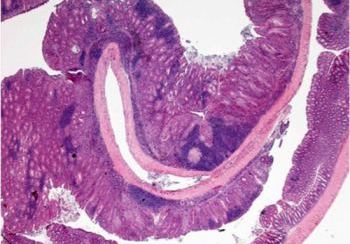

Una de las asociaciones mejor documentadas entre inflamación crónica y tumorogénesis se da en el cáncer colorectal de pacientes que padecen inflamación del intestino.

El cáncer colorectal es el tercero más común en el mundo. Los pacientes con la enfermedad de inflamación de intestino, ya sea por colitis ulcerosas o por colitis de Crohn, tienen un riesgo más elevado de desarrollar este tipo de cáncer.

En un artículo reciente, el equipo de Ángel R. Nebreda describe como p38α es fundamental para el mantenimiento de la buena salud del epitelio intestinal, controla la severidad de las colitis y actúa de supresor de tumores en el colon.

El objetivo principal de este proyecto es investigar como p38α regula la tumorogénesis colorectal asociada a colitis. Los resultados permitirán entender el papel de p38α y sus efectores en la biología del cáncer, así como la interacción entre las células epiteliales y del tejido, a fin de estimar su valor como diana terapéutica o marcador de diagnóstico.